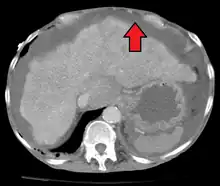

Diagnosis

Routine complete blood count (CBC), basic metabolic profile, liver enzymes, and coagulation should be performed. Most experts recommend diagnostic paracentesis if the ascites is new or if the person with ascites is being admitted to the hospital. The fluid is then reviewed for its gross appearance, protein level, albumin, and cell counts (red and white). Additional tests will be performed if indicated such as microbiological culture, Gram stain, and cytopathology.[8]

The serum-ascites albumin gradient (SAAG) is probably a better discriminant than older measures (transudate versus exudate) for the causes of ascites.[11] A high gradient (> 1.1 g/dL) indicates the ascites is due to portal hypertension. A low gradient (< 1.1 g/dL) indicates ascites of non-portal hypertensive as a cause.[12]

Ultrasound investigation is often done before attempts to remove fluid from the abdomen. This may reveal the size and shape of the abdominal organs, and Doppler studies may show the direction of flow in the portal vein, as well as detecting Budd–Chiari syndrome (thrombosis of the hepatic vein) and portal vein thrombosis. The sonographer also can estimate the amount of ascitic fluid, and difficult-to-drain ascites may be drained under ultrasound guidance. An abdominal CT scan is more accurate than a sonogram to reveal abdominal organ structure and morphology.[12]